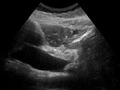

The major duodenal papilla, seen on duodenoscopy at the time of ERCP. This is the protrusion of the ampulla of Vater into the duodenum.